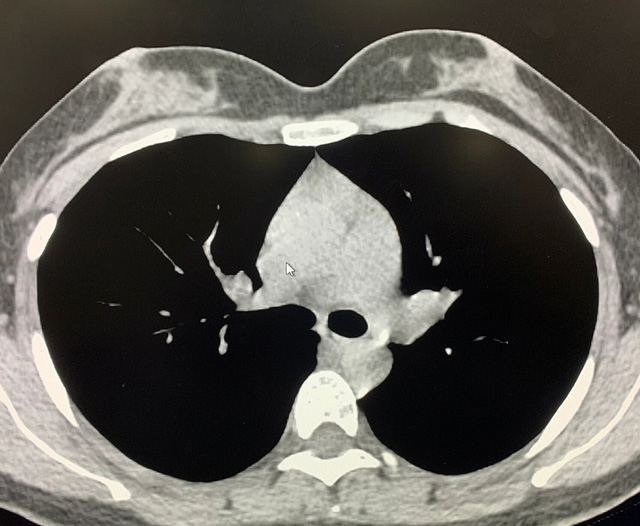

能譜純化技術(shù)CT低劑量胸部掃描

能譜純化技術(shù)的核心是通過(guò)物理濾過(guò)(如錫濾片)或軟件算法,選擇性濾除低能X射線光子,保留高能光子。在胸部低劑量CT掃描中顯著提升了圖像質(zhì)量與輻射劑量的平衡。

1.明顯降低患者的輻射劑量,能譜純化后,使重疊無(wú)用的X線濾除。

2.明顯提高圖像質(zhì)量,高能光子穿透力強(qiáng),光子通量更均勻,圖像噪聲(標(biāo)準(zhǔn)差)可降低20%-40%。

3.能譜純化技術(shù)相比于低千伏低劑量技術(shù),可以有效消除線性硬化偽影,提高診斷效能;

優(yōu)勢(shì)輻射劑量顯著降低相較于常規(guī)CT,輻射劑量減少約70%-90%,尤其適合需多次隨訪的高危人群(如肺癌篩查),降低輻射相關(guān)癌癥風(fēng)險(xiǎn)早期肺癌篩查效果明確可清晰檢測(cè)毫米級(jí)肺結(jié)節(jié),顯著提高早期肺癌檢出率,降低死亡率。檢查快捷且普及性高單次掃描僅需數(shù)秒,無(wú)需對(duì)比劑,設(shè)備廣泛配置于基層醫(yī)院,便于大規(guī)模篩查。長(zhǎng)期成本效益顯著雖單次費(fèi)用與常規(guī)CT相近,但早期干預(yù)可大幅降低晚期治療費(fèi)用及社會(huì)醫(yī)療負(fù)擔(dān)。技術(shù)優(yōu)化提升圖像質(zhì)量迭代重建算法(如ASIR、MBIR)在降低劑量同時(shí)減少噪聲,平衡影像質(zhì)量與安全性。